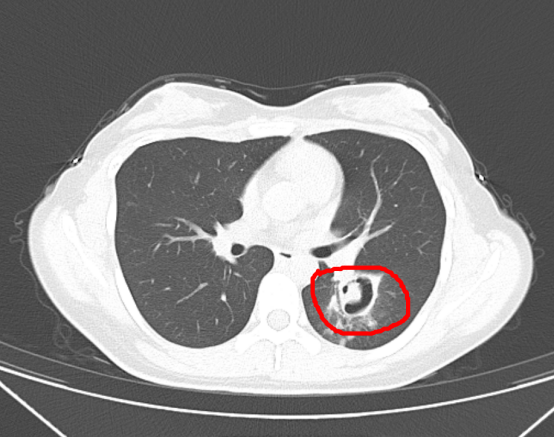

接诊的感染性疾病科(肝病科)周翔主任医师从肺部CT上发现,王女士的肺部长出了一个个“小树芽”,怀疑是霉菌性肺炎。

为了进一步确诊病情,周翔为王女士做了纤维支气管镜检查,果然发现气道壁上缀着大量白色菌斑,化验后确认是曲霉菌。